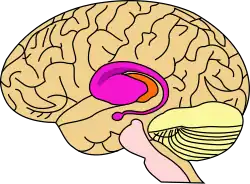

| Imagem microscópica editada de neurónios espinhosos médios (amarelo) com corpúsculos de inclusão (laranja), que ocorrem como parte do processo da doença | |